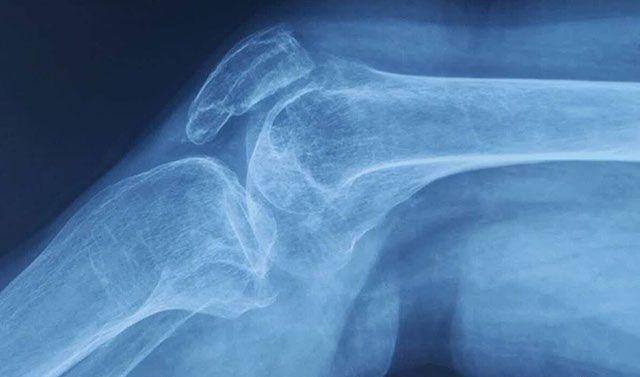

Trichorhinophalangeal综合II型(TRPS II)是由8号染色体的长(q)臂上的遗传物质的缺失引起的.TRPS II是引起骨和关节畸形的病症; 独特的面部特征; 智力残疾; 和皮肤,头发,牙齿,汗腺和指甲的异常。TRPS II的体征和症状与染色体这一部分的多个基因的丢失有关。删除的大小因受影响的个体而异; 研究表明,较大的缺失往往导致比较小的缺失更多的特征。

该TRPS1,EXT1,和RAD21基因缺失在人与TRPS II。研究人员已经确定,EXT1基因的缺失是造成TRPS II患者的多种良性(非癌)骨肿瘤的原因,称为骨软骨瘤。该损失TRPS1基因被认为是导致其他骨骼和面部畸形。删除RAD21基因可能会导致智力残疾。来自8号染色体区域的其他基因的丢失可能有助于这种情况的额外特征。